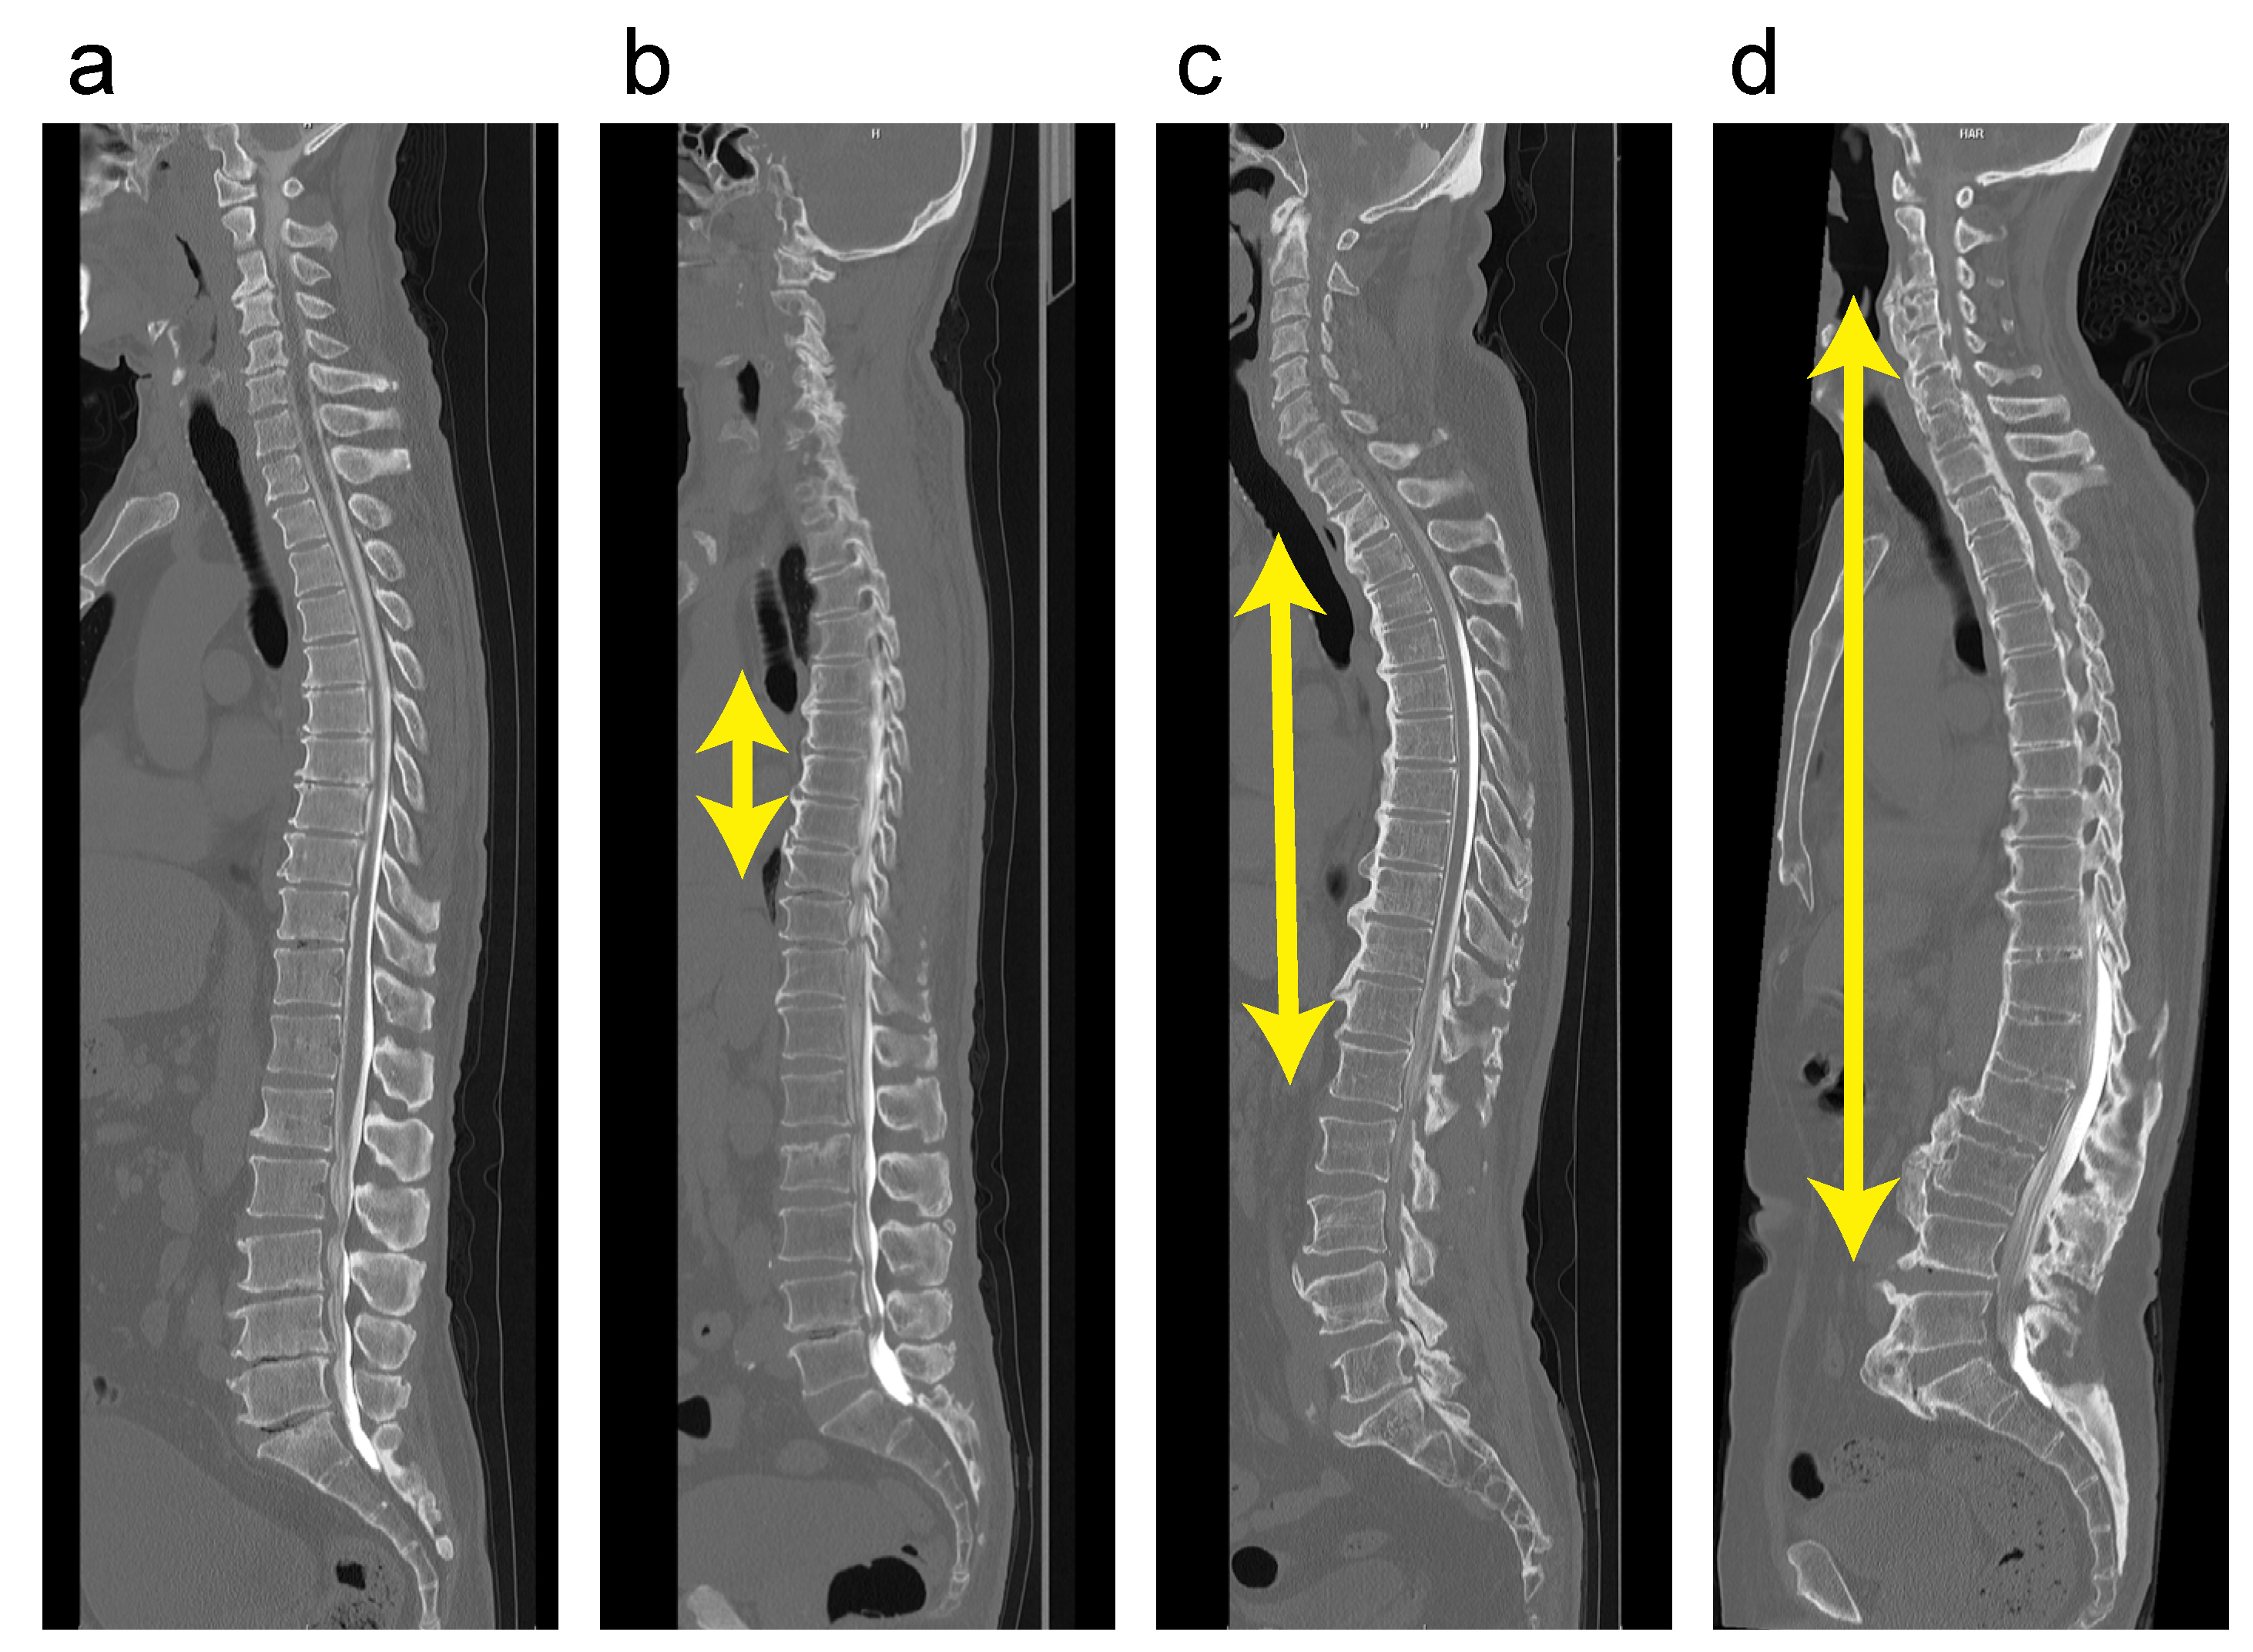

3.3. Case Presentation